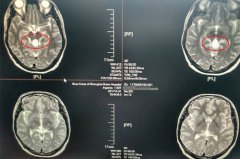

惊! 18岁少女不明原因突发脑出血 神经外科专家沈建康教授确诊并成功完成手术

2017年7月3号,对18岁的的倩倩(化名)来说,是一个开心的日子。在上海蓝十字脑科医院做完手术后的第13天,她终于可以和爸爸妈妈一起回家了。 倩倩在出院前和爸爸妈妈在一起 花季少女突然头痛不止 自从去年9...【详细】